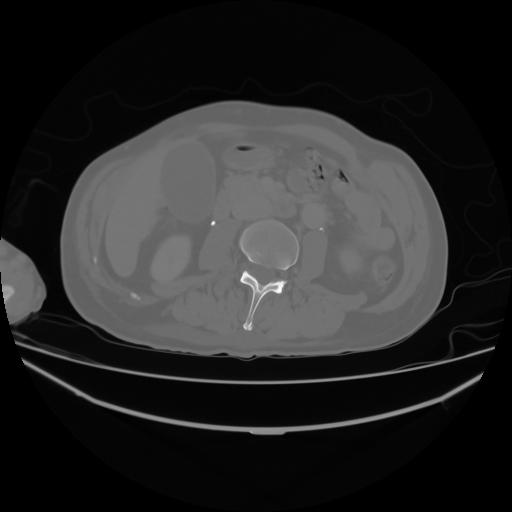

4 CUERPO,CE,Axial,3.0,CUERPO,,